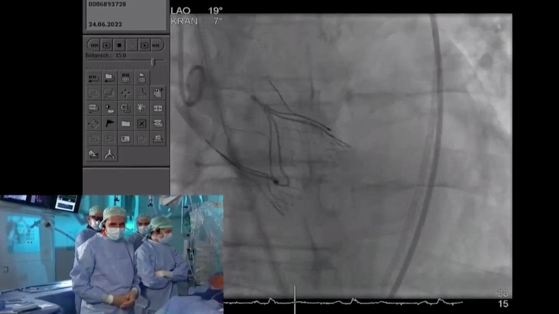

来自德国University Hospital Mainz的Hendrik Treede教授Alexander Tamm教授带来的一例症状性主动脉瓣反流患者的TAVI手术直播,患者为65岁男性,因呼吸困难就诊,纽约心功能分级III级,近期因前降支重度狭窄行PCI,同时合并肾功能受损及高血压。TTE/TEE超声结果显示为右窦脱垂导致的重度主动脉瓣反流,左室扩张,左室射血分数轻度降低。Hendrik Treede教授详尽地讲解了Trilogy系统的步骤操作,并完整展示了器械植入的全流程,手术取得了极佳的结果,良好的血流动力学,术毕造影及超声结果显示无主动脉瓣反流,无瓣周漏。术后讨论中,Hendrik Treede教授与Alexander Tamm教授再次肯定了整个系统的精巧设计,Trilogy独有的定位键可实现与原生瓣叶对齐,同时为瓣叶无钙化的单纯反流病例提供锚定。其瓣膜流出端超大网孔设计和瓣叶定位技术也为冠脉再介入带来优势。随着器械应用和经验的积累,瓣膜选择策略更加适配患者情况,改善因瓣膜选择过大和植入过深导致的传导阻滞。